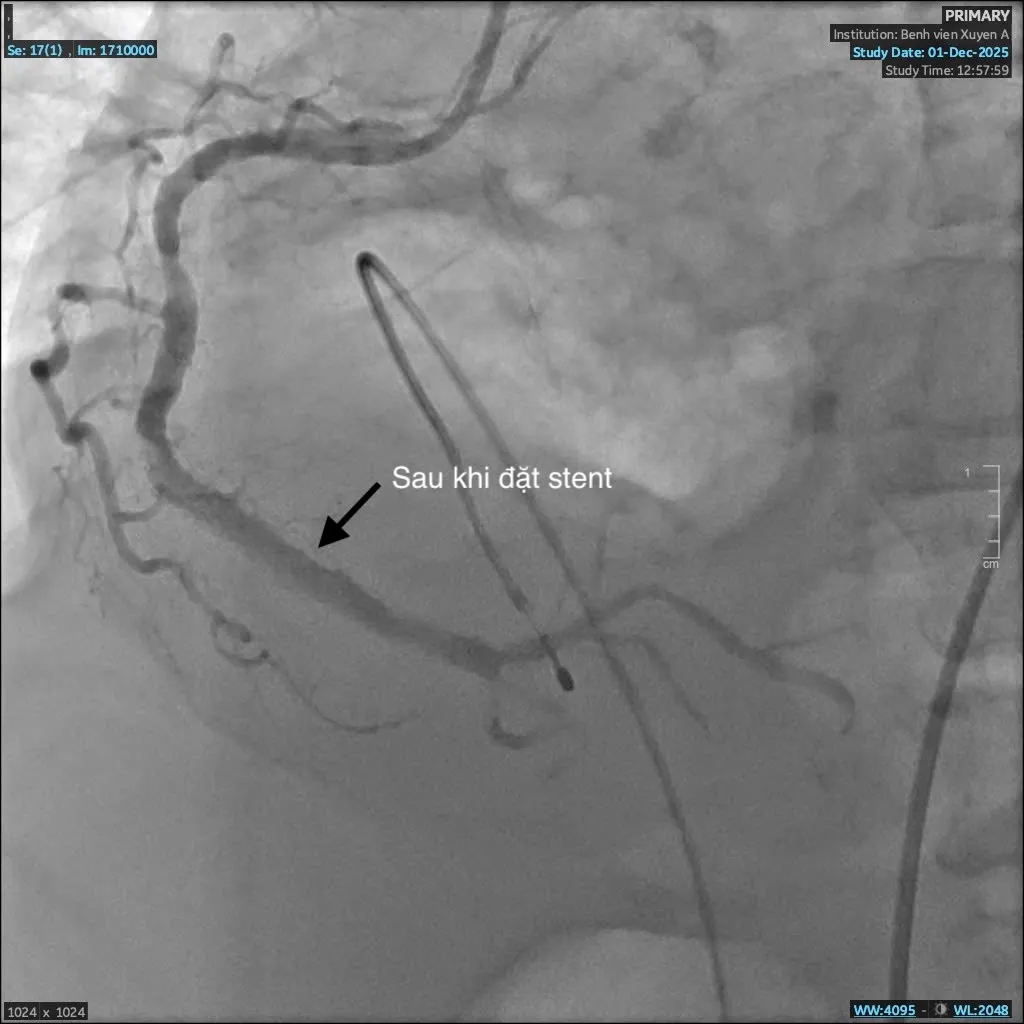

Với bệnh lý nhồi máu cơ tim nguy hiểm này, nếu không được phát hiện và can thiệp kịp thời, người bệnh sẽ rơi vào nguy cơ sốc tim, rối loạn nhịp dẫn đến tử vong. Không chần chừ, các bác sĩ khoa Can Thiệp Tim Mạch quyết định can thiệp nong và đặt stent động mạch vành nhằm tái thông dòng máu nuôi tim.

Sau can thiệp, tình trạng huyết động của bệnh nhân dần ổn định, triệu chứng khó thở giảm rõ rệt, người bệnh qua cơn nguy kịch. Bệnh nhân tiếp tục được theo dõi sát và điều trị tích cực tại khoa Can Thiệp Tim Mạch, kết hợp kiểm soát các bệnh lý nền như tăng huyết áp, đái tháo đường và suy thận.

Sau can thiệp stent, tái thông được mạch máu

Bác sĩ Giản Tư Trí - khoa Can Thiệp Tim Mạch Bệnh viện đa khoa Xuyên Á cho biết: “Bệnh nhân C. có tiền căn hen phế quản vào viện trong tình trạng suy hô hấp, việc chẩn đoán gặp nhiều khó khăn. Trong quá trình can thiệp, dưới hướng dẫn của hệ thống số hóa xóa nền DSA, ê-kíp nhận thấy mạch vành của bệnh nhân bị vôi hóa nhiều do đái tháo đường, suy thận lâu năm. Vôi hóa là “kẻ thù” của can thiệp mạch vành, gây khó khăn cho việc nong và đặt stent, thậm chí khiến việc can thiệp thất bại. Nhưng với sự tỉ mỉ và kinh nghiệm xử trí nhiều ca đặt stent phức tạp trước đó, các bác sĩ khoa Can Thiệp Tim Mạch đã vượt qua thách thức và đặt stent thành công, tái thông mạch máu nuôi tim, cứu bà C. qua cơn nguy kịch.”